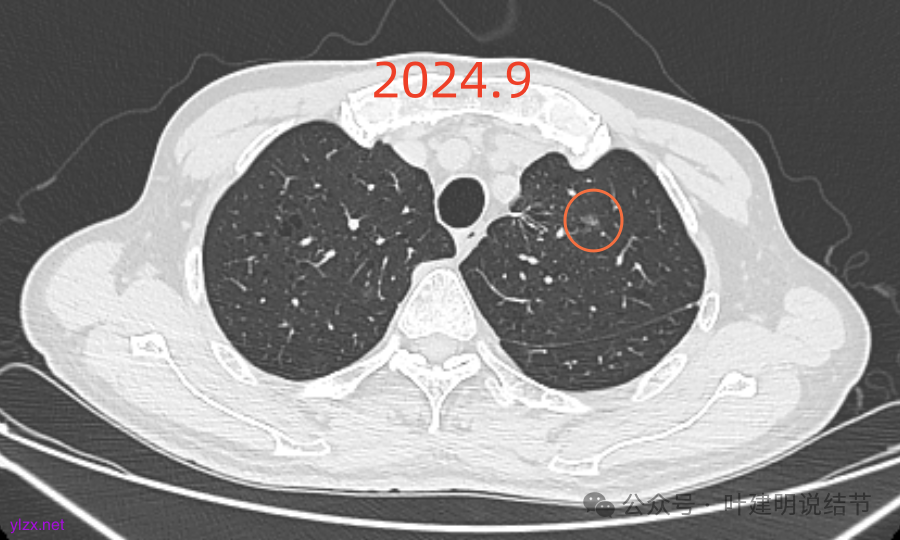

再看2024年9月复查的:

右上的仍小而淡,轮廓仍是清楚的。

左上的病灶略显模糊,密度不太纯,较前相仿。